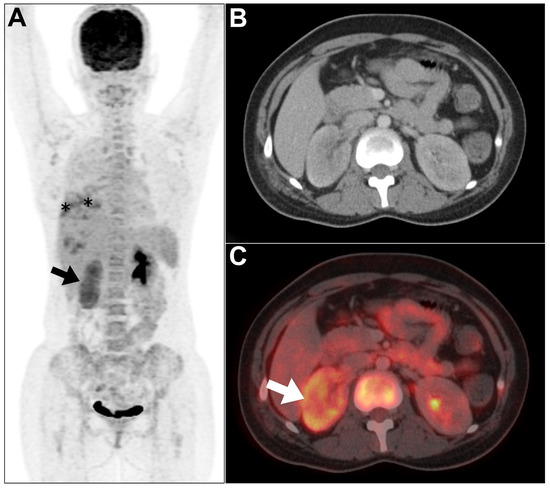

2.1.1. Acute Pyelonephritis

2.1.2. Infective Polycystic Kidney Disease

2.3.2. Renal Abscess